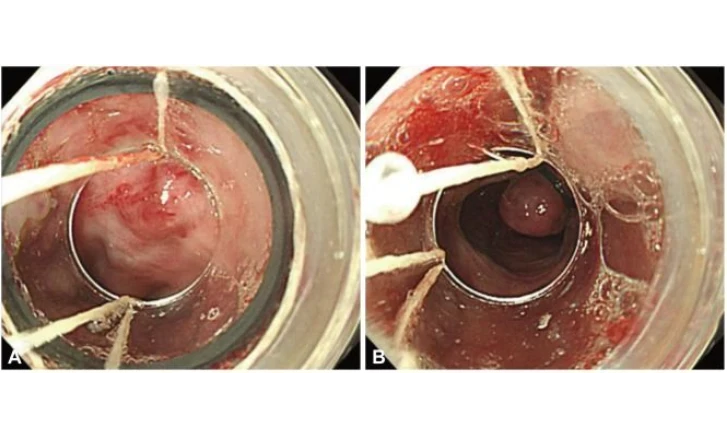

- POEM

- POEM and Gastric-POEM (Peroral Endoscopic Myotomy)